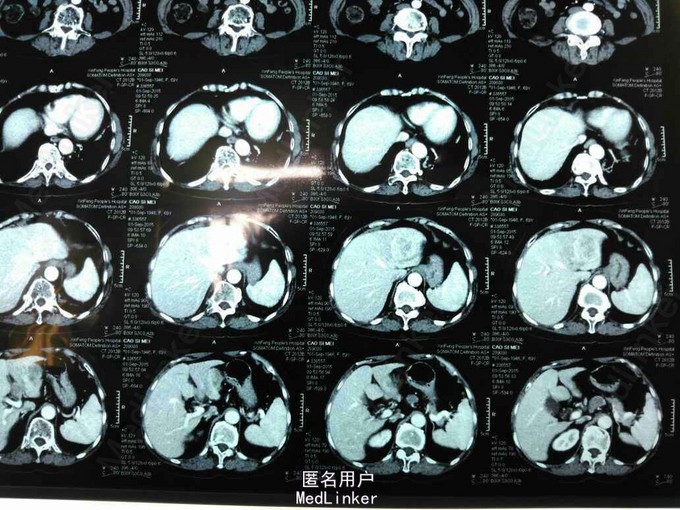

患者,女性,69岁,因“右上腹疼痛不适2月余”入院。

查体无特殊。辅查:腹部增强CT提示肝左外叶癌。AFP:92948ng/ml。

诊断:原发性肝左外叶癌。治疗:肝癌切除术。